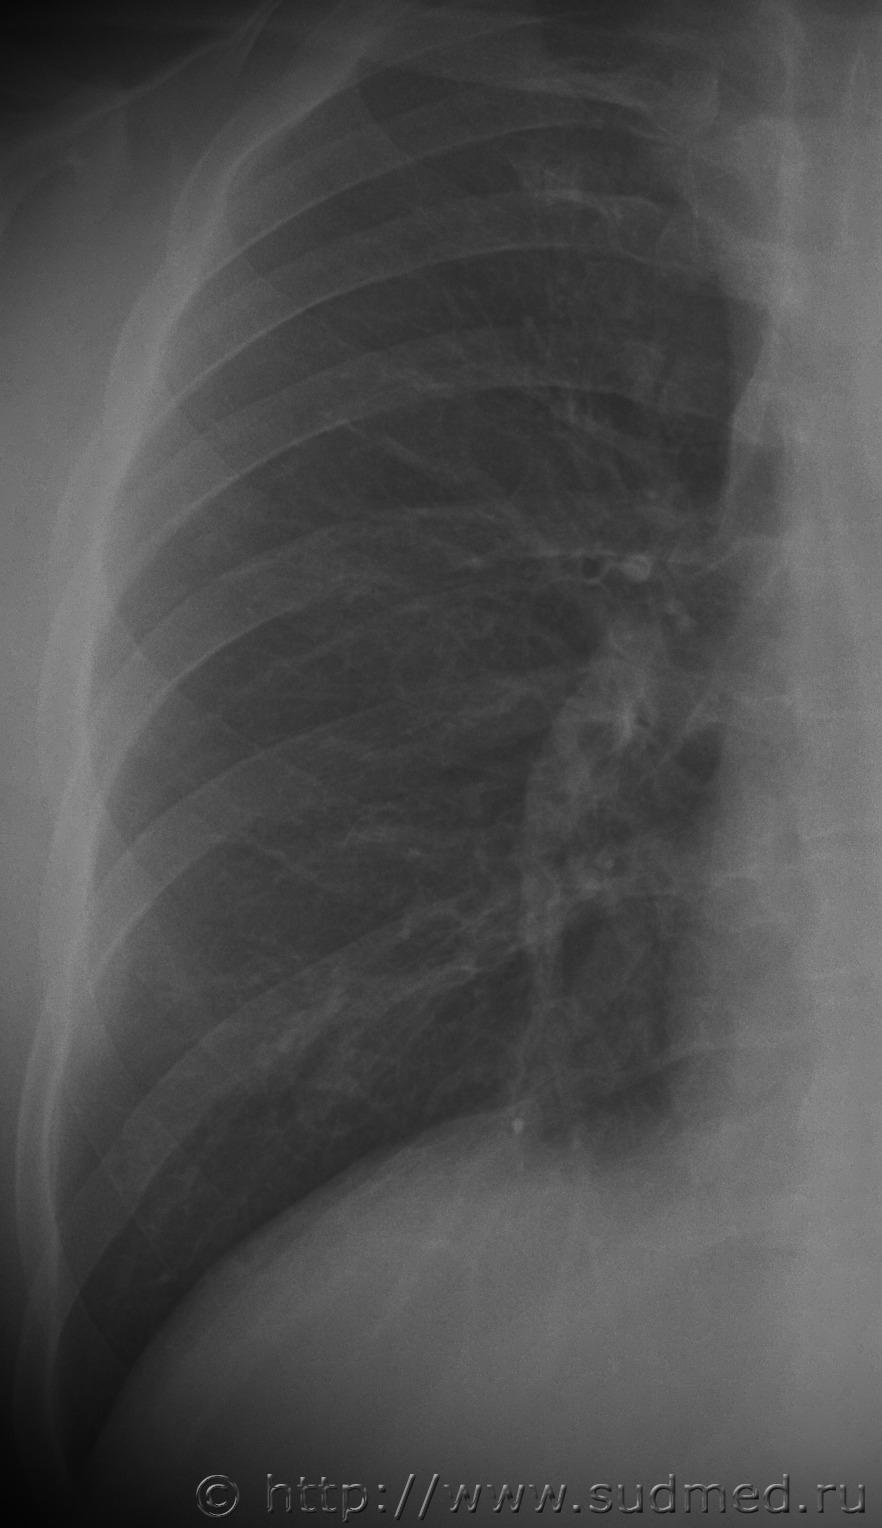

Давность переломов ребер |

Некоторое время назад проводил экспертизу, у потерпевшего были переломы 8-10 ребер справа, ожидается что, может возникнуть вопрос по давности их образования, прикладываю предоставленные мне рентгеновские снимки. Какие мнения?

Радомир Изменений 8 и 10 ребер не вижу. Оч.похоже на постт... 18.11.2016 - 21:53

мужик с батоном На 9-м ребре справа по задней подмышечной линии им... 18.12.2016 - 10:13

Norman Свежих переломов нет. Даже на счёт консолидированн... 2.04.2017 - 07:02![]() ![]() |